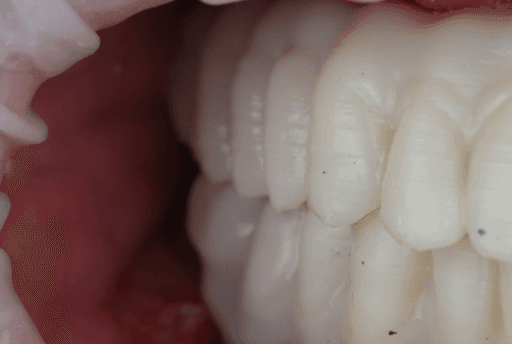

The temporary MUA screw-retained prosthesis were installed in the patient's mouth and occlusion was checked. From the clinical perspective, occlusal contacts required minimal correction as the occlusion was already accurately planned in the CAD software. The patient expressed comfort and reported to be satisfied with the esthetic outcome.

A carefully controlled occlusal scheme with reduced posterior contacts was adopted to minimize overload during osseointegration. The patient was instructed to follow a soft diet during the initial healing phase.

Upper, lower, and occlusion check of the temporary full-arch implant-supported appliances.

Close-up photo of immediate clinical outcome

At the five-month follow-up appointment, clinical evaluation revealed healthy and stable peri-implant soft tissues in both arches. The mucosa showed good adaptation around the provisional prostheses, with no signs of inflammation, suppuration, or peri-implant pathology.

The provisional restorations maintained adequate function and esthetics throughout the healing phase, confirming the reliability of the guided implant placement and immediate loading protocol.

Intraoral view five months after procedure

Five-month follow-up (intraoral view)